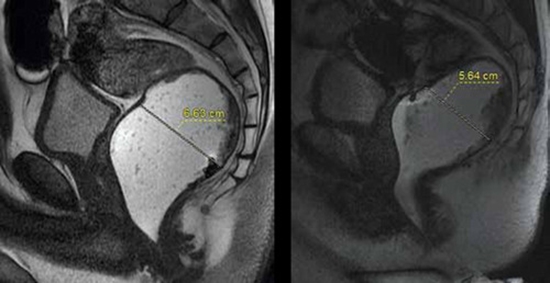

بررسی تاثیر بیوفیدبک تراپی نسبت به درمان استاندارد بر روی شاخصهای ام آر دفیکوگرافی در بیماران مبتلا به سندرم انسدادی دفع :در یک مطالعه کارآزمایی بالینی موازی دو سوکور تصادفی

مقایسه بیوفیدبک و درمان استاندارد در سندرم انسدادی دفع